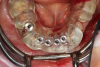

Case 2. Smile Zone Implant: Single Maxillary Central Incisor

Providing single-tooth restorations in the smile zone can be challenging; considerations for implant dentistry for a single maxillary incisor can be even more challenging. For this case, the digital workflow considerations were not much different from the previous case; radiographs, photography, and analog impressions were used. The patient was given alternative treatment options. He chose a single implant and final zirconia with cutback for porcelain application. The patient was advised about his surrounding vintage dentistry and told he should consider all maxillary anterior teeth, Nos. 6 through 11, be planned for better function and esthetics. The patient had the final say, which allowed the laboratory and the author to finalize the treatment plan with the definitive restoration.

Properly planning this case with digital dental technology offered a large quantity and quality of diagnostic information. Using the dental laboratory software to merge the entire 3D data set helped to predict the best outcome after the digital proposals for the implant abutment and final crown. The patient had been involved with implant dentistry and understood the value of technology available.

Figure 6 and Figure 7 depict a mature smile with many implant restorations. An analog impression was sent to the laboratory. The impression was scanned by the laboratory, a model was created virtually, and the implant dimensions and position were defined. The 3D surgical guide was fabricated (Figure 8), allowing the patient to receive his therapy swiftly and predictably. Tooth No. 8 was extracted, and the implant was placed and immediately loaded with an acrylic provisional treatment crown (Figure 9). The screw-retained treatment crown was fabricated in-office from a previously completed diagnostic wax-up.

After 4 months of healing and integration of the bone around the implant, the digital workflow was initiated to develop the abutment and treatment plan. Another analog impression was made with an impression post and polyvinyl impression. The laboratory scanned the impression and digitized it to create the emergence profile of the milled titanium abutment and the final restoration (Figure 10 and Figure 11). The patient had a considerably thick soft-tissue profile, allowing a milled titanium abutment. The decision to use a titanium abutment was based on the patient's occlusion and propensity to fracture teeth or restorations. The virtual model was gray because the scanner does not recognize the color of the analog impression. The virtual final abutment and crown were approved and fabrication completed. The final restoration met the patient's esthetic values and his ability to function (Figure 12 and Figure 13).

Fig 6. Image of the patient’s mature smile.

Figure 6

Fig 7. Radiograph showing the patient’s multiple implant restorations.

Figure 7

Fig 8. 3D-printed surgical guide.

Figure 8

Fig 9. Surgery day with immediately loaded implant and treatment crown.

Figure 9

Fig 10. Titanium abutment proposal.

Figure 10

Fig 11. Final crown proposal.

Figure 11

Fig 12. Six months after cementation.

Figure 12

Fig 13. Radiograph 6 months after cementation.

Figure 13